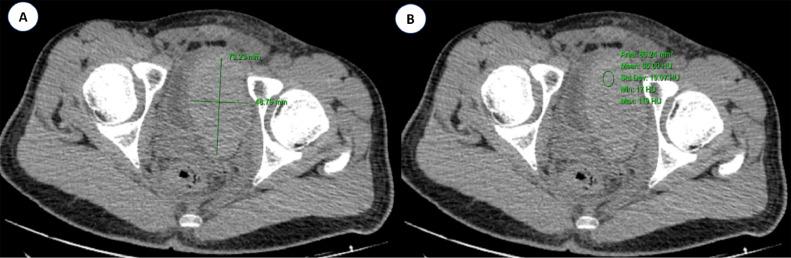

经栓塞治疗的腹膜后脂肪肉瘤急性出血

Acute hemorrhage from a retroperitoneal liposarcoma treated by embolization.

Liposarcomas are rare retroperitoneal mesenchymal tumors that present at an advanced stage and often have poor prognoses. These malignant tumors create a diagnostic conundrum and pose several treatment difficulties due to their rarity and anatomic placement. Retroperitoneal liposarcomas often present as asymptomatic abdominal tumors and rarely cause acute bleeding. Surgery is typically required in cases with acute malignant bleeding and hemodynamic instability. Angioembolization and other bleed-control methods should be researched where available. This case report describes the case of a 17-year-old male patient whose tumor had an acute abdominal hemorrhage treated by embolization.

摘要